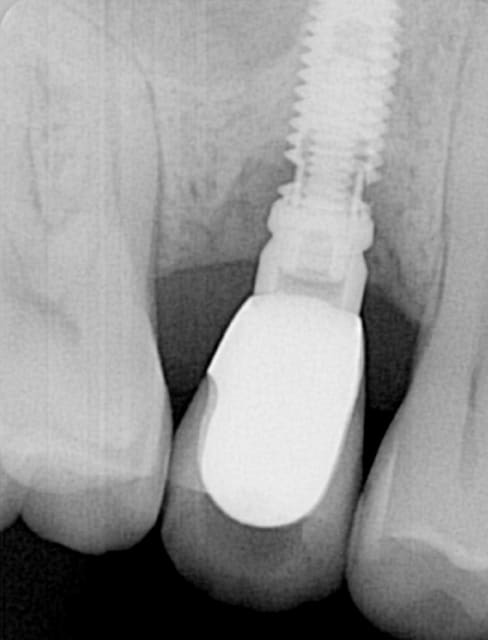

Comment j'enlève ça à votre avis??

patiente pas du tout bruxo, occlusion parfaitement réglée et contrôlée à 6 mois.

J'ai posé au CA blocage à 40N on peut pas dire que ce soit violent.

Celui de Fred fait 3,3 de diamètre, ça peut casser (cf radios de Straumenn 3,3, ou analogue fracturé sur le site du Dr. Ajou).